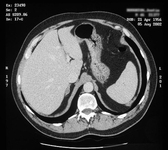

TC mostrando lesão na glândula adrenal direita em paciente com adenoma produtor de aldosterona no lado direito

Do acervo pessoal do Dr. Michael Stowasser; usado com permissão